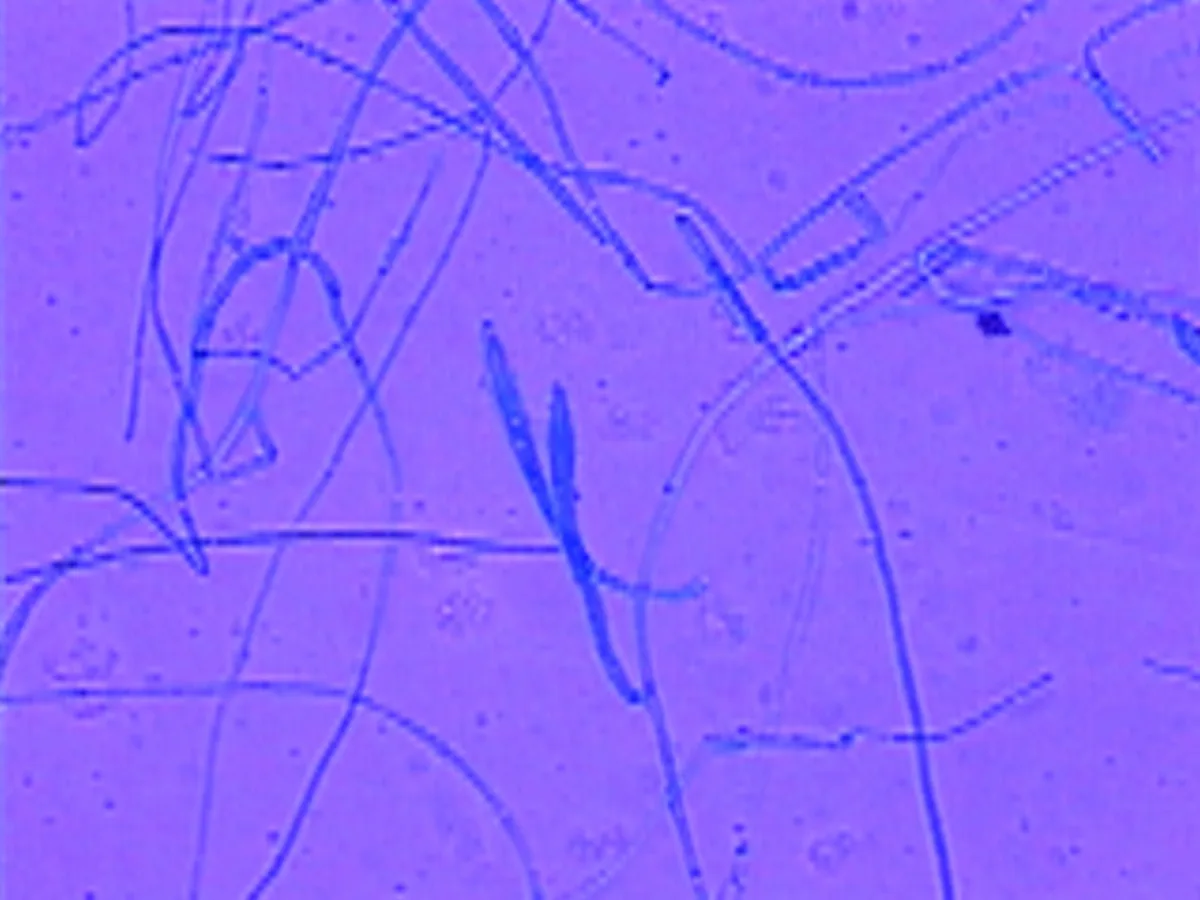

I examine all slides at low power in order to find areas where the hyphae have stained well; then move to a higher power for final examination. M gypseum produces large numbers of macroconidia (A). M canis produces fewer macroconidia (B), and the walls are thicker and rough.

If the laboratory temperature is too cold, M canis may not sporulate and all that will be seen are hyphae with thick, finger-like projections on the ends (C). This is evidence that the colony is trying to sporulate. Increasing the temperature in the laboratory will help speed the process.